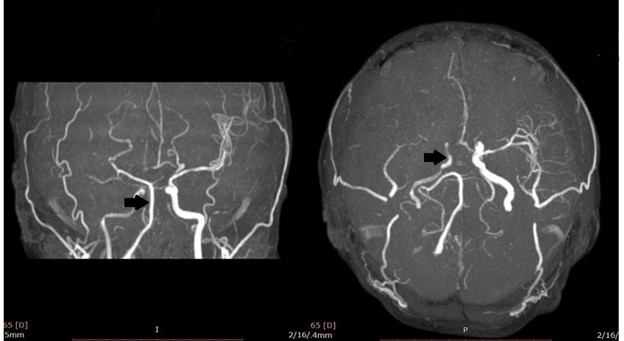

A non-contrast CT scan initially provided inconclusive results, prompting diffusion-weighted MR brain imaging, revealing an acute middle cerebral artery stroke (Figure 1). Subsequent MRI brain with MR venography demonstrated additional findings, including asymmetrical cavernous sinus and narrowed right internal carotid artery (Figure 2). Consequently, MRA of the carotid vasculature revealed a hypoplastic right internal carotid artery and abnormal appearances of the middle cerebral and anterior cerebral arteries, presenting as a beaded appearance at the petrous (C2), lateral, and cavernous (C4) segments, with collateral filling through the circle of Willis (Figure 3).

Figure 3. MRA showing a hypoplastic right internal carotid artery (ICA) with non-visualization of the M1 and M2 segments of the right middle cerebral artery (MCA).